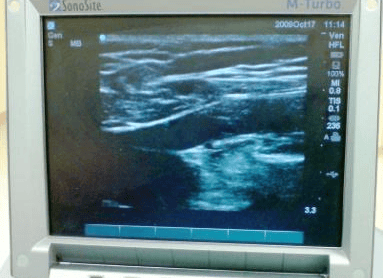

At your initial 30 min consultation the vascular surgeon who will perform a vein scan (doppler scan) to assess you further and decide the best way to treat your veins. This will involve putting some gel on your leg which can easily be washed off later. The surgeon will expose your whole leg from groin downwards to check your leg veins thoroughly. If you require a chaperone please let the doctor know.

Diagnosing which veins are faulty guides the vascular surgeon on how to treat the vein so this step is very important and is key to success of subsequent treatment. This scan is painless and is similar to scan in pregnancy. It does not involve X-rays.